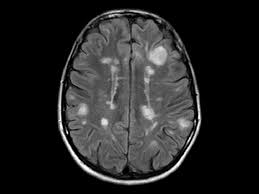

Widespread use of mri (magnetic resonance imaging) has revolutionized the ability to diagnose multiple sclerosis. Optic nerve evaluation within normal limits. Magnetic resonance imaging (mri) plays a crucial role in multiple sclerosis (ms) diagnosis, disease monitoring, prognostication, and research. There are multiple lesions in the spinal cord. Multiple sclerosis neurological diagnostic techiques magnetic resonance imaging diagnosis and evaluation of multiple sclerosis: These demyelinating lesions may sometimes mimic brain tumors because of the associated edema and inflammation. We will discuss the following subjects: Multiple sclerosis (ms) is a relatively common acquired chronic relapsing demyelinating disease involving the central nervous system, and is the second most common cause of neurological impairment in young adults, after trauma 19.characteristically, and by definition, multiple sclerosis is disseminated not only in space (i.e. Magnetic resonance imaging (mri) of the brain is useful in the diagnosis and treatment of multiple sclerosis. An mri scan is abnormal in more than 95% of people recently diagnosed with ms. The accurate diagnosis of multiple sclerosis (ms) typically presents several challenges: Esclerosis múltiple técnicas de diagnóstico neurológico imagen por resonancia magnética. Lo que el radiólogo debe conocer e informar.

Balo Concentric Sclerosis Radiology Reference Article Radiopaedia Org from prod-images-static.radiopaedia.org An mri scan is abnormal in more than 95% of people recently diagnosed with ms. Abnormalities show up on scans from many illnesses other than ms. Conventional magnetic resonance imaging (mri) has routinely been used to improve the accuracy of multiple sclerosis (ms) diagnosis and prognosis. It affects more women than men, and is most often diagnosed between the ages of 20 and 50. Usually, mri is the only imaging modality needed for imaging patients with ms, and it far surpasses all other tests. Its high sensitivity for the evaluation of inflammatory and neurodegenerative processes in the brain and spinal cord has made it the most commonly used technique for the evaluation of patients with ms. To describe the factors that are associated with gadolinium enhancement on mri in patients with multiple sclerosis (ms) and symptoms of relapse. There are multiple lesions in the spinal cord.

These demyelinating lesions may sometimes mimic brain tumors because of the associated edema and inflammation. Multiple sclerosis (ms) is a common central nervous system (cns) disease characterised pathologically by the development of multifocal inflammatory demyelinating white matter lesions. 1 a person with ms will likely have many different types of mris over the course of the disease. The cns includes the brain, spinal cord, and optic nerves. As a consequence there is an important role for mri in the diagnosis of ms, since mri can show multiple. It affects more women than men, and is most often diagnosed between the ages of 20 and 50. Conventional magnetic resonance imaging (mri) has routinely been used to improve the accuracy of multiple sclerosis (ms) diagnosis and prognosis. Multiple sclerosis (ms) is the most common inflammatory. To describe the factors that are associated with gadolinium enhancement on mri in patients with multiple sclerosis (ms) and symptoms of relapse. Multiple lesions in different regions of the brain) but also in time. Optic nerve evaluation within normal limits. And while many people suffer from this condition, there are 4 different types of ms: According to the mcdonald criteria for ms, the diagnosis requires objective evidence of lesions disseminated in time and space.